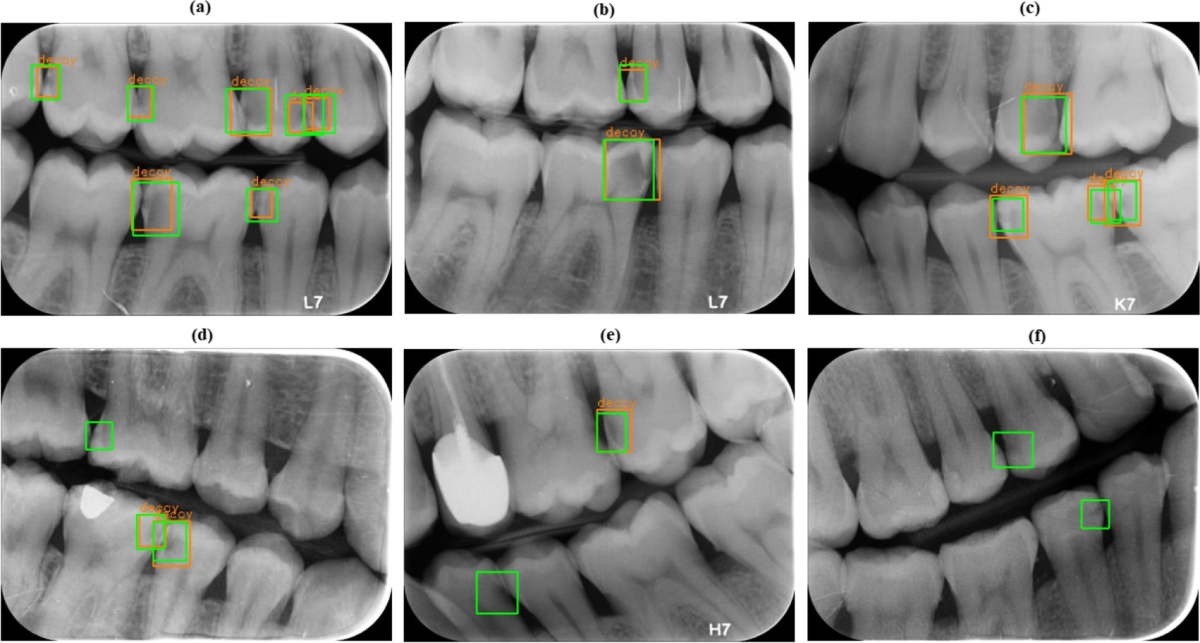

Early Interproximal Caries Detection

The Challenge

Incipient lesion on distal of #14 missed by initial visual inspection due to tight contact point.

AI Finding

DentalVision AI flagged a 0.85 confidence radiolucency in the enamel-dentin junction.